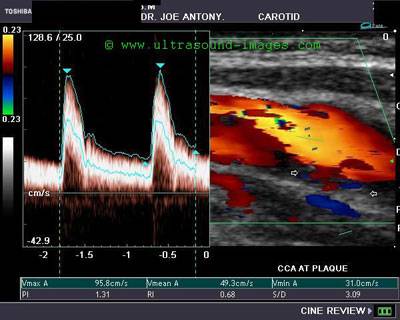

Допплерография сосудов головы и шеи совмещает в себе ультразвуковые методы исследования и допплеровский эффект. По сути, происходит следующее: во время стандартной ультразвуковой диагностики, отраженные волны формируют изображение строения сосудистых стенок. Допплеровский эффект позволяет увидеть в динамике движение крови по сосудам. Компьютерная техника позволяет совмещать эти два изображения и давать окончательную полноценную визуализацию обследуемой области.

Кроме того, в процессе для большей наглядности используется кодирование цветовыми оттенками. В таких исследованиях выделяют 2 основных направления: транскраниальное УЗДГ — это диагностика сосудистого бассейна мозга и УЗДГ брахиоцефальных сосудов — это диагностика сосудов, расположенных в области шеи.

На УЗ-мониторе это отражается в виде цветного изображения разнонаправленных потоков крови – красных (положительный сдвиг) и синих (отрицательный сдвиг). Метод УЗДГ БЦА имеет как положительные, так и отрицательные стороны. К положительной следует отнести возможность обследования транскарниальных оделов головного мозга, то есть артерий, находящихся внутри черепной коробки, в то время как для классического ультразвукового исследования (β-режима) эта зона является недоступной.

Дуплексное сканирование брахиоцефальных артерий выполняется на ультразвуковых сканерах последнего поколения, совмещающих классическое УЗИ в β-режиме и допплерографию. Оценку состояния артерий и качество кровотока производят, основываясь на двухмерном (дуплексное сканирование) или трехмерном (триплексное сканирование) изображении. При этом сосуд может отображаться в поперечной плоскости и в длину.

Важно! Цветной доплеровский режим отражает информацию о качестве кровотока, а спектральный режим используют для получения количественной информации.